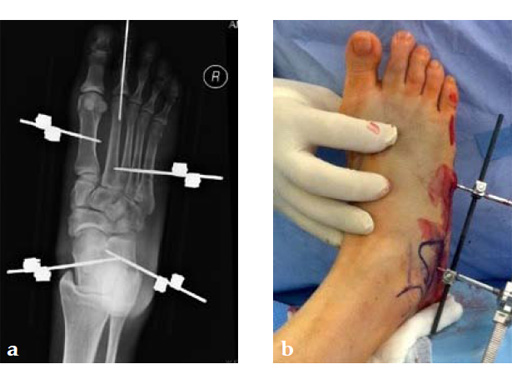

A 46-year-old obese woman with coronary artery disease had sustained a Lisfranc injury while performing an exercise program. She was unable to weight bear and used an electric scooter.

In an effort to restore her ability to exercise and taking into consideration her body weight and upper extremity weakness, a decision was made to use the variable angle locking compression plate. These postoperative x-rays were obtained at 3 months, one month after beginning weight bearing. The patients pain was reduced and she was able to resume a progressive exercise program after 4 months following surgery.

Case provided by Michael Castro, Scottsdale, Arizona